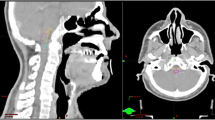

Overall, the MRI findings in the brainstem injury patients revealed a continuous spectrum of RT-associated damage. Small solid enhanced nodules were evident in four cases, while moderate and large lesions were apparent in other cases (lesions were classified as described in Table 1). The evolution of radiotherapy-induced brainstem injury was well documented; the MRI features of brainstem injury (including signal abnormality on T1 and T2 images) resolved completely in three patients following gradual improvement over two months. However, one patient developed a large contrast-enhanced lesion, with a central necrotic core in the base of the pons; this was the only patient with brainstem injury who died (Fig. 2).

Necrosis nidus within the brainstem and the corresponding dose distribution. Contrast-enhanced lesion (white arrow) in the axial (a) and sagittal (c) view on post-contrast T1-weighted MRI images with a 53-year-old NPC patient (the 5th patient in Table 1). Corresponding isodose lines are shown in b and d, respectively

In this study, brainstem injury lesion occurred most frequently in the proximal or top portion of the pons, extending to the midbrain and medulla oblongata. It may be related to the anatomical structure of the brainstem. The pons easily accepts higher doses; in areas that are located in the posterior closest to the basilar clivus, rather than the other areas, the occurrence of radiation brainstem injury is likely greater. However, lesion sites did not all occur in the most anterior portion of the pons. Four patients’ sites were located on both sides of the pons. The dose of the lesion site in 8 cases was less than its Dmax, suggesting that the occurrence of brainstem injury may be closely related to the brainstem dose per unit volume, so D0.1cc and D1cc were used as indicators to evaluate brainstem injury in this study.